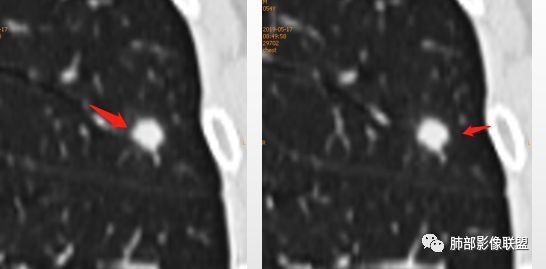

1、与炎性假瘤、恶性肿瘤鉴别:恶性肿瘤边缘膨隆,收缩也是毛毛糙糙的,炎性假瘤收缩力较强,边缘凹陷的多。隐球菌孤立结节收缩力弱,膨胀力也弱,与胸膜关系多为糊墙,部分有间隙。右边两幅可以看到胸膜增厚,胸膜下脂肪间隙增宽。晕中长毛刺,边缘平直,血管走行自然,鉴别肺癌。

2、与结核鉴别:

3、与淋巴结鉴别:淋巴结小于1cm,多位于胸膜下。结节周围不应该有晕,可以与血管相连,与胸膜有多条影相连

4、与曲霉鉴别:曲霉少见孤立性病灶,除非寄生性的。出现长毛刺和晕则往往见于免疫力下降病例。曲霉不强化。血管炎孤立的少,一般是多态多灶,周围长索条,一般是包膜样强化。